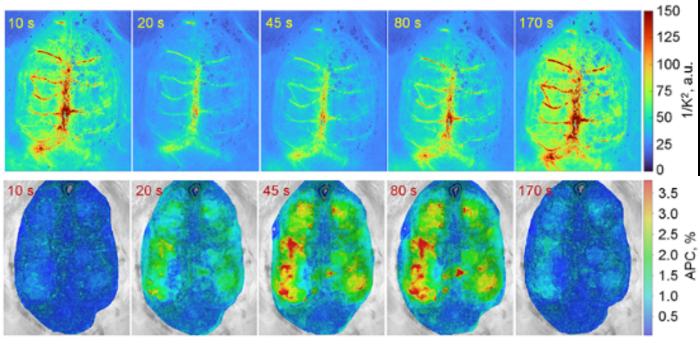

LSCI emphasizes large surface veins and heartbeat-locked speckle changes (top raw); IPPG emphasizes tissue pulsations (bottom raw). Beat-normalized time courses from both methods co-evolve, revealing an initial dip and a delayed rise in perfusion.